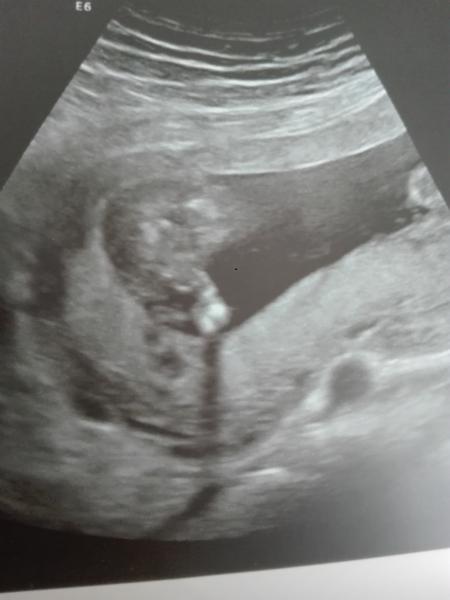

Hallo an die August mamis ich bin in der 16 ssw und et lautet 24.08.17 Ich Hätte da mal eine frage ich hatte heute morgen einen FA Termin er sagte evtl ein junge sie wolle sich noch nicht festlegen also ich erkenne nichts schaut mal und sagt doch bitte was ihr da seht :D

Bild zu Outing - Forum für August - Mamis

Ich kann leider nichts erkennen . Bin aber auch echt schlecht darin :)